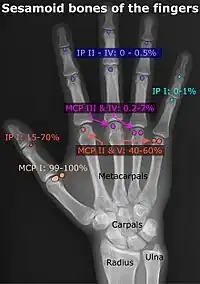

Poignet et main

| Os accessoire | Prévalence à droite (R) et à gauche (L) [3] |

|---|---|

| Os ulnostyloideum | 1,5 % R, 2,4 % L |

| Os central du carpe | 1,3 % R, 2,1 % L |

| Os trapèze secondaire | 0,5 % R, 2,1 % L |

| Os styloïdeum | 1,2 % R, 1,2 % L |

| Os radiale externum | 1 % R, 0,9 % L |

| Os triangulare | 1 % R, 0,9 % L |

| Os paratrapezium | 0,3 % R, 0,9 % L |

| Os capitatum secondaire | 0,8 % R, 0,3 % L |

| Os hypotriquetrum | 0,5% R |

| Os hypolunatum | 0,3%L |

| Os épilunatum | 0,3% R, 0,3% L |

| Os ulnare externum | 0,3%L |

| Os pisiforme secondaire | 0,3% R |

| Os epitrapezium | 0,3%L |

| Os vesalianum manus | 0,3%L |